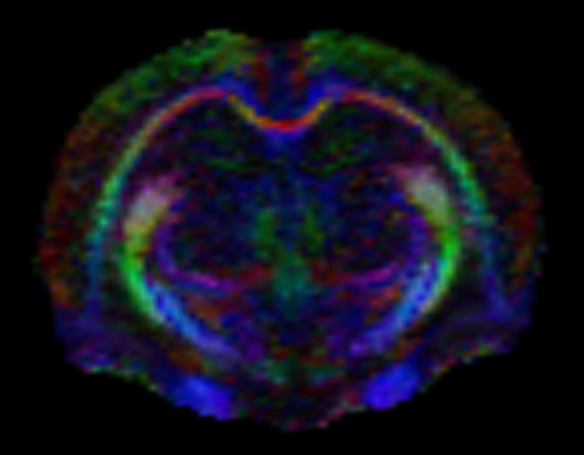

Boğaziçi Üniversitesi Hedefli Tedavi Teknolojileri Merkezi (Boğaziçi CT3) Deney Hayvanları Görüntüleme Birimi, Türkiye’nin ilk preklinik (deney hayvanlarında kullanım için özelleşmiş) 7T MRG (manyetik rezonans görüntüleme) cihazının yanı sıra preklinik BT (bilgisayarlı tomografi) ve hem MRG hem de BT tarayıcıları ile entegre edilerek PET-MRG ve PET-BT çalışmalarına olanak tanıyan PET tarayıcısı ile araştırmacılara ve sektördeki kuruluşlara eşsiz bir altyapı sunmaktadır.

Birimimizde; tüm vücut ve bölgesel MR taramaları, doku karakterizasyonu, metabolik görüntüleme, moleküler hedeflerin izlenmesi ve farmakokinetik değerlendirmeler gerçekleştirilebilmektedir. Ayrıca hayvan kabul ve karantina alanlarımız, uluslararası etik standartlara uygun olarak yapılandırılmıştır.

Yüksek alan kuvveti sayesinde sağlanan üstün görüntü kalitesi ve hassasiyet, özellikle onkoloji, nörobilim, kardiyovasküler ve farmasötik araştırmalarda büyük avantajlar sağlamaktadır. Araştırmalarınıza özgü deneysel protokoller geliştirme, planlama ve analiz süreçlerinde, deneyimli teknik ekibimizle kapsamlı destek sunuyoruz.